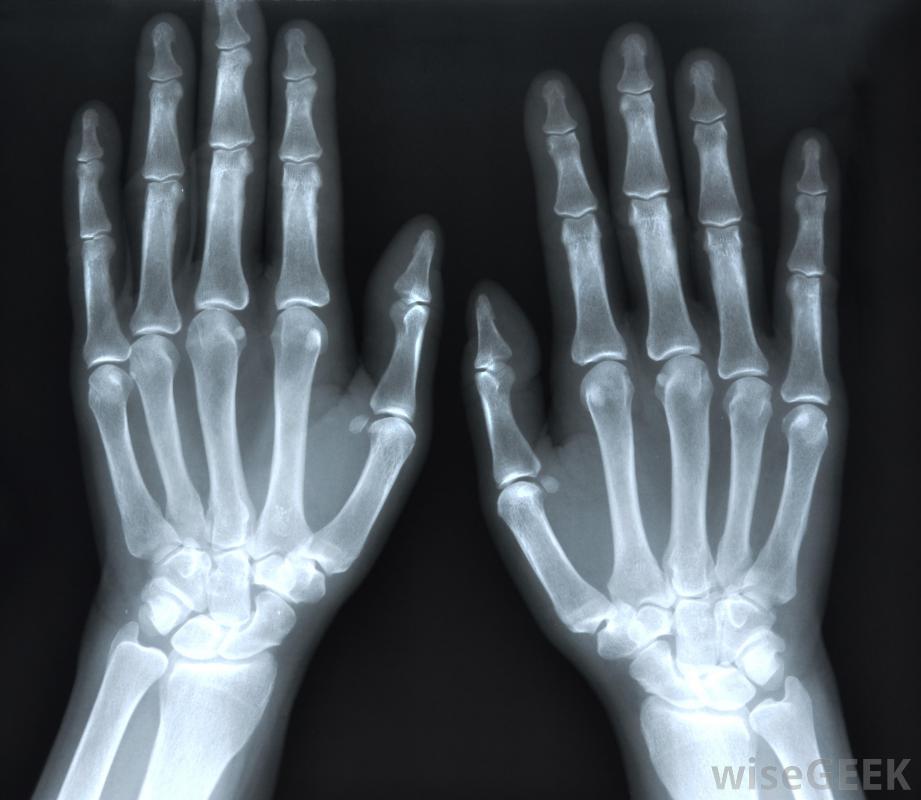

膠原蛋白疾病是一個術語,指的是與膠原蛋白有關的疾病,膠原蛋白是一種存在于多種結締組織中的蛋白質。膠原蛋白非常堅韌,具有膠狀的稠度。它占人體內蛋白質的30%左右,是人體物理結構的重要組成部分。涉及膠原蛋白的疾病可以導致各種健康問題。類風濕性關節炎是系統性自身免疫性疾病的一個例子在歷史上,這個術語被用來指結締組織疾病,也被稱為系統性自身免疫性疾病。人們有時把這種情況稱為"膠原血管疾病"。這個術語的用法被認為是過時的,但仍然出現在一些舊的教科書和醫學圖表中。一些系統性自身免疫的例子疾病包括類風濕性關節炎、系統性紅斑狼瘡、硬皮病和皮肌炎在顯微鏡下檢查。在真正的膠原疾病中,膠原蛋白本身也參與了疾病的進程。膠原蛋白會發炎,這可能導致結締組織的破壞,從而導致關節等問題疼痛、酸痛、壓痛和肌肉無力這通常是因為免疫系統錯誤地將膠原蛋白識別為入侵者并開始攻擊它。膠原蛋白在反應中分解,身體可能難以替換受損的膠原蛋白。X光可能會為了診斷關節炎而服用。一些膠原缺陷是遺傳性的。某些先天性疾病會干擾產生膠原的能力。許多患有遺傳性結締組織疾病的人會這樣做沒有產生足夠的膠原蛋白,無法產生正確種類的膠原蛋白,或過度生產膠原蛋白。先天性的膠原蛋白疾病會導致結締組織的問題,從而導致從器官損傷到肌肉矮小或虛弱等各種問題可注射藥物可用于緩解由膠原疾病引起的關節疼痛。也可獲得膠原疾病。某些類型的感染與膠原蛋白,包括可以引發自身免疫性疾病的疾病,人體開始自我攻擊。由于反復受傷、癌癥、對藥物的反應和其他事件,人們也可以發展成膠原蛋白紊亂硬皮病是一種結締組織疾病,其特征是皮膚和結締組織變硬和變緊。當醫生懷疑病人患有膠原疾病時,活檢可能會要求在顯微鏡下檢查受累區域的結締組織。將進行完整的病史檢查和身體檢查。這些信息將用于診斷,以便醫生討論該疾病的治療或處理。對于某些情況,目前尚無有效的治療方法,治療的重點是控制癥狀,保持患者舒適,并監測患者是否有并發癥的跡象。自體免疫性疾病的治療,如膠原蛋白疾病,通常包括各種藥物的混合物。